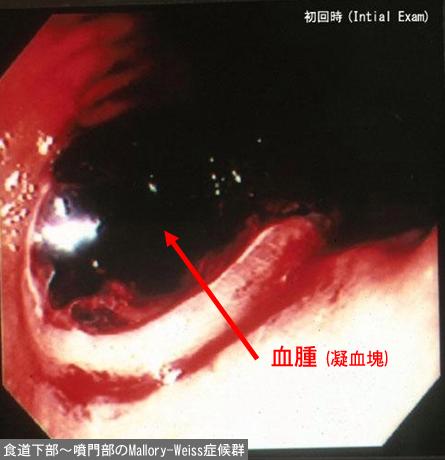

Comparative diagnosis of inflammatory disease at the boundary region of the digestive tract.

Esophagus/Lower third

Endoscopy